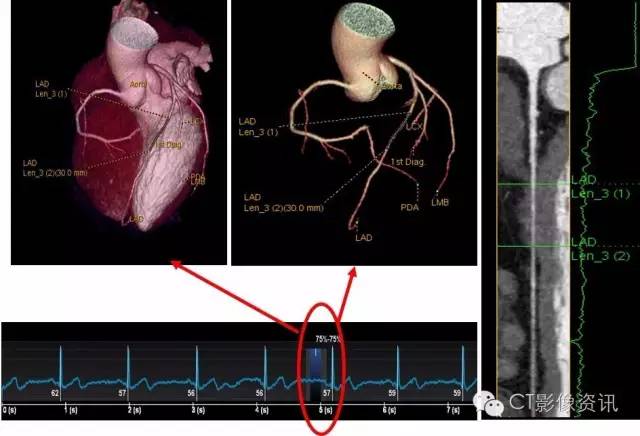

您看看这心跳的节律,一会儿53,一会儿116,让扫描老师咋办?这种极不规则的心率对常规的设备就是一场惊心动魄的挑战!假如扫描时落在低心率时,成功率比较高;假如扫描时落在高心率时,有可能不成功,假如扫描时不幸落在正在活跃的R波上,那就可能导致重做的风险!假如……,噢,现在不用假如了,我用Revolution CT就行了!

经过8天的使用,目前我们共进行CCTA扫描114例数,其中心率低于70者仅占44例,中高心率41例,心律不齐29例。接近一半的检查对于传统不够宽度、时间分辨率不够的CT来说都面临着非常大的压力,而Revolution CT致力于解决行业面临的困境,统统卸掉其它CT的压力包袱,彻底释放,所有挑战的检查都在一个心跳之内完成,实在是惊艳了我们所有放射科的同仁!Revolution CT的极致之心果然名不虚传啊!而且更加厉害的是,这些检查减少了对患者配合度的要求,例如今天一位80多岁的老爷爷进行术前评估时,不用憋气就能进行CCTA检查,大大方便了检查者和操作者。